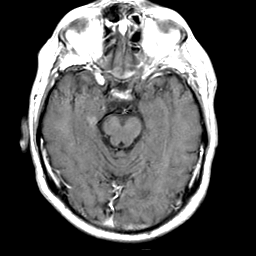

Meningioma, MR Study #2 -- Slice #7

[Home][Help][Clinical] Slice 7